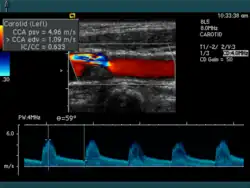

Für die Beurteilung der Gefäße und der Durchblutung kommt Ultraschall in Form von Doppler- und Duplexsonographie zum Einsatz.

Die Aussagekraft der Sonografie kann erheblich durch die Anwendung des Doppler-Effekts erhöht werden. Man unterscheidet eindimensionale Verfahren (Pulsed-Wave-Doppler, Continuous-Wave-Doppler, auch als D-mode bezeichnet) von zweidimensionalen, farbkodierten Anwendungen (Farbdoppler – F-mode). Die Kombination B-Bild mit Pulsed-Wave-Doppler (PW-Doppler) nennt man auch Duplex.[4]

Doppler-Verfahren werden benutzt zur Bestimmung von Blutfluss-Geschwindigkeiten, zur Entdeckung und Beurteilung von Herz(klappen)fehlern, Verengungen (Stenosen), Verschlüssen oder Kurzschlussverbindungen (Shunts), siehe Farbkodierte Doppler-Sonografie.

Aus ihrem Vorzeichen lässt sich die Flussrichtung rekonstruieren. Bei gegebener Geschwindigkeit ist die Frequenzverschiebung umso größer, je größer die Sendefrequenz ist. Im Bereich von 2 bis 8 MHz und Flussgeschwindigkeiten von wenigen mm/s bis zu 2 m/s ist etwa 50 Hz bis 15 kHz. Zur exakten Geschwindigkeitsmessung ist die Bestimmung des Winkels (Doppler-Winkel) zwischen Schallausbreitungsrichtung und Bewegungsrichtung des Erythrozyten (Richtung des Blutgefäßverlaufes) notwendig. Da das Doppler-Prinzip winkelabhängig ist und die Kosinus-Funktion in die Geschwindigkeitsberechnung eingeht, kommt es infolge des sich mit zunehmendem Winkel ändernden Anstiegs der Kosinus-Funktion zu unterschiedlich starken Einflüssen gleicher Winkelmessfehler auf die errechnete Geschwindigkeit. Da sich Bewegungen des Schallkopfes in der Realität kaum vermeiden lassen, nehmen die Fehler, die durch diese Variation des Winkels entstehen, überproportional zu, wenn der Winkel zwischen Schallausbreitung und Gefäßrichtung untersuchungsbedingt variiert. Daher wird allgemein empfohlen, Aussagen zu Geschwindigkeiten bei Untersuchungen mit einem Doppler-Winkel > 60° zu unterlassen. Die Abhängigkeit vom Winkel lässt sich aber eliminieren, beispielsweise durch Verwendung von Stereomessköpfen.

Bei der farbkodierten Doppler-Sonografie wird für einen großen Bereich eines konventionellen Ultraschallbildes (Color-Window) die örtliche Doppler-Frequenz (= mittlere Flussgeschwindigkeit) und deren Schwankungsbreite bestimmt. Damit möchte man die Turbulenz der Strömung abschätzen. Aufgrund der statistischen Bewegungen der Streuteilchen ist die Schwankungsbreite der Fließgeschwindigkeit jedoch stets größer als die Turbulenz. Das Ergebnis wird in Falschfarben auf dem B-Bild überlagert, also in Farbtönen von rot und blau für verschiedene Blutgeschwindigkeit und grün für Turbulenz. Hierbei steht üblicherweise die Farbe Rot für Bewegung auf den Schallkopf zu, während mit blauen Farbtönen Flüsse weg von der Sonde codiert werden. Bereiche der Geschwindigkeit 0 werden durch die Elektronik unterdrückt.

Farb-Doppler und PW-Doppler. Innerhalb der Stenose ist wegen der hohen Flussgeschwindigkeit und des resultierenden Alias-Effekts die Geschwindigkeit in Blau kodiert.

Farb-Doppler und PW-Doppler. Innerhalb der Stenose ist wegen der hohen Flussgeschwindigkeit und des resultierenden Alias-Effekts die Geschwindigkeit in Blau kodiert. -